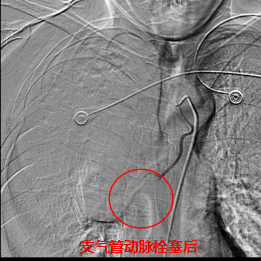

术中,数字减影血管造影(DSA)显示患者右侧支气管动脉及胸廓内动脉增粗紊乱,末梢血管可见造影剂点状外溢,明确为主要出血责任血管。团队采用400 µm栓塞微球及560–710 µm明胶海绵颗粒,对出血动脉远端实施精准栓塞,实现“末梢血管封堵”;同时,对肺动脉分支血栓相关区域也予以栓塞处理,以全面控制咯血来源。术后造影确认出血完全停止,患者安返病房后未再咯血,胸闷、气促等症状显著缓解。